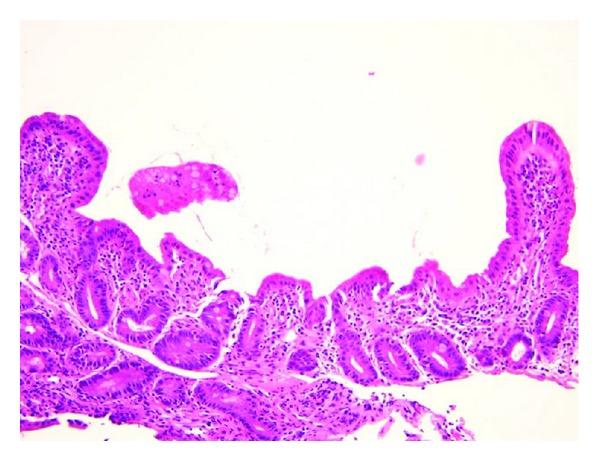

Mycophenolate mofetil (MMF) is an immunosuppressive medication utilized in the management of both autoimmune and solid organ transplant patients. Diarrhea is a common gastrointestinal side effect of MMF, but more severe forms of GI symptoms are described in renal transplant patients with a distinct pattern of histopathologic change, similar to graft-versus-host disease or Crohn's disease. This rare entity, commonly referred to as "MMF-related enterocolitis," has been described in adult patients, mostly in renal transplant patients, and in only two pediatric renal transplant patients. In previously reported cases, symptoms and abnormal histopathology improve with dose reduction of MMF. We describe a series of three pediatric patients with varied underlying disease process who presented with severe diarrhea and histopathologic findings characteristic of MMF-related enterocolitis, who share a novel finding of weight loss as a complication of MMF-related enterocolitis in pediatric patients.

https://cdn.ncbi.nlm.nih.gov/pmc/blobs/cf87/3485763/12bc79870eb9/CRIM.PEDIATRICS2012-624168.001.jpg